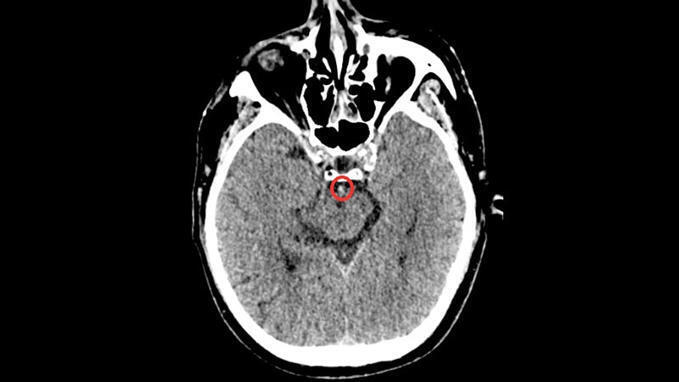

Early Flow-Diverter Implantation in Ruptured Intracranial Aneurysms: Safety and Outcomes in a Resource-Limited Setting neurointervention.org March 16, 2026, 9:56 a.m.

Early FD implantation in carefully selected ruptured aneurysms, including small saccular and morphologically complex lesions can achieve high functional recovery and complete angiographic occlusion, even in a resource-limited environment. Ideal case selection and standardized DAPT and hemodynamic protocols are critical. These findings support broader use in challenging aneurysms, but larger prospective studies are warranted to validate outcomes and refine management strategies.

Early Flow-Diverter Implantation in Ruptured Intracranial Aneurysms: Safety and Outcomes in a Resource-Limited Setting neurointervention.org March 11, 2026, 3:08 p.m.